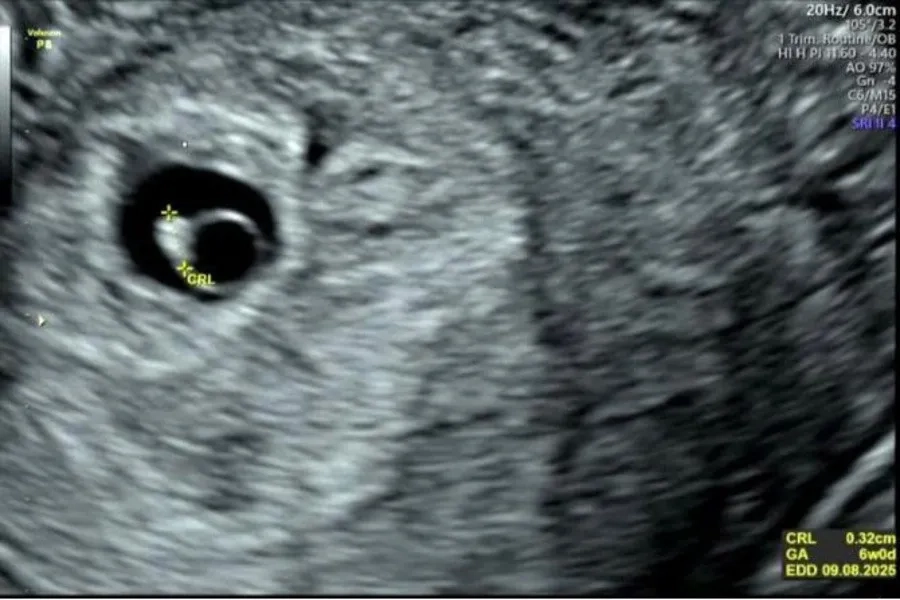

Hình ảnh túi ối nhỏ hơn so với tuổi thai

Ở giai đoạn tuần 6–8, một số trường hợp túi ối nhỏ nhẹ có thể tự cải thiện khi mẹ bầu điều chỉnh chế độ dinh dưỡng và được theo dõi sát bằng siêu âm. Tuy nhiên, nếu tình trạng kéo dài hoặc đi kèm với các bất thường khác (như không thấy tim thai, túi ối biến dạng...), đây là dấu hiệu cần can thiệp y tế sớm.